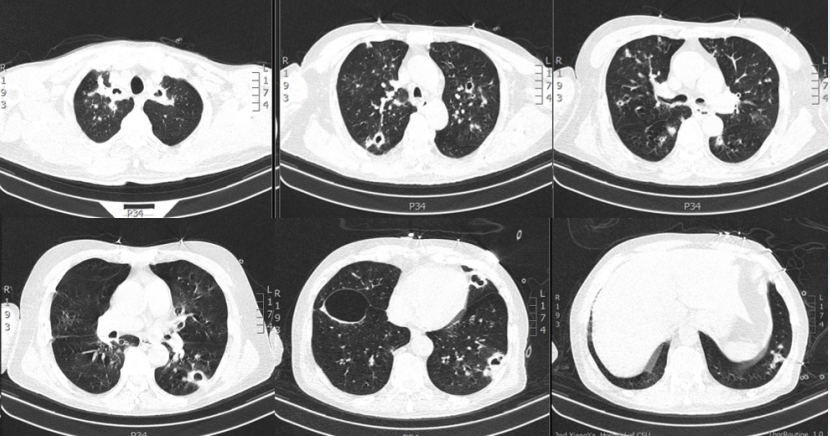

6月20日,待患者情况稳定后复查胸部CT:较6月6日出现新的病变(图12)。再次启动两性霉素B胆固醇酯质复合物(50~100~150 mg/d)抗真菌,同时予头孢哌酮舒巴坦+多黏菌素B(静脉+雾化)抗细菌治疗。

图片

12  患者胸部CT(2023-06-20)